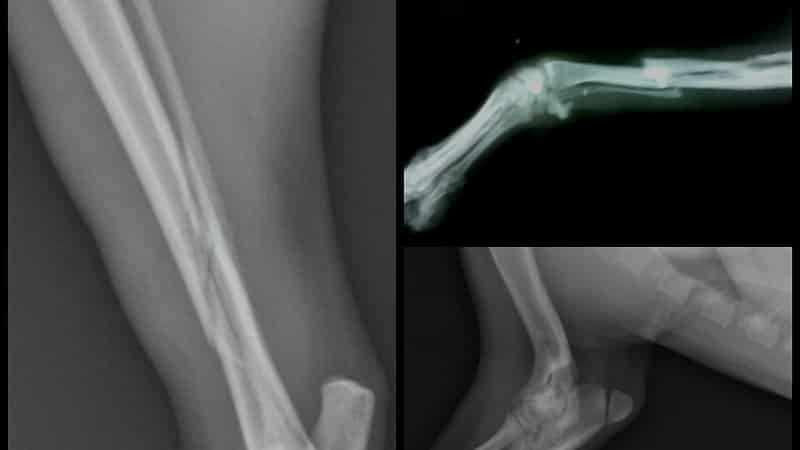

На приеме хирург или травматолог проводит первичный осмотр, записывает жалобы, узнает о том, как пациент получил травму, и дает направление на рентген. Это стандартный метод диагностики трещин и переломов, который позволяет получить данные о виде повреждения, увидеть, как выглядит трещина в кости на снимке, ее размер и состояние тканей.

Тактика лечения зависит от точности постановки диагноза. В тяжелых и сложных случаях для определения характера повреждений используют магнитно-резонансную томографию, позволяющую создавать 3D-изображения с определением глубины надкола кости.